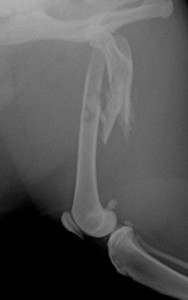

LCP1.5を使用して整復した、トイプードルの橈尺骨骨折の治療例

術前